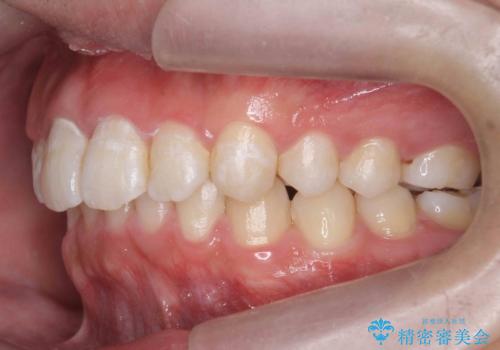

出っ歯が気になる 歯をぬかずに治療

- 前歯が出ているのを気にして来院。

左のかみ合わせが1本分ずれていましたが、機能的には問題ないのでそのまま変えずに治療しています。

ずれている分を、上の歯を1本抜くか(ワイヤー矯正になります)、右上の奥歯を1本分後ろに送るか、そのまま前歯を並べるのかを選んでいただきました。

右のかみ合わせをそのままに、最小限の動かし方で見た目を改善しました。